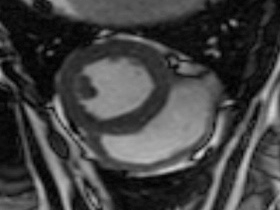

Easy-Trigger ist ein Medizinprodukt für die Herz- und Gefäßbildgebung in der Magnetresonanztomographie (MRT), das bifunktional bei Ungeborenen und Erwachsenen eingesetzt werden kann. Als weltweit erstes und einziges MRT-taugliches Doppler-Ultraschallgerät ermöglicht es erstmals Kombinationsuntersuchungen von MRT und Ultraschall. Der Ultraschallkopf wird auf dem Bauch oder über dem Herzen des Patienten platziert. Es ermöglicht erstmals die zeitliche Abstimmung der Herzaktion von ungeborenen Kindern mit dem MRT und damit MRT-Untersuchungen des kindlichen Herzens. Des Weiteren kann es zur Überwachung der Ungeborenen bei MRT-Untersuchungen von Schwangeren eingesetzt werden. Durch die Verwendung der Doppler-Ultraschall-Technik ist die Anwendung am Erwachsenen im Vergleich zum EKG robuster, einfacher und sogar bei höheren Feldstärken einsetzbar, bei denen das EKG nicht mehr zuverlässig arbeitet.

- Kording F, Yamamura J, Much C, Adam G, Schoennagel B, Wedegärtner U, Ueberle F.:

Evaluation of an MR Compatible Doppler-Ultrasound Device as a New Trigger Method in Cardiac MRI: A Quantitative Comparison to ECG.

Biomed Tech (Berl). 2013 Sep 7.